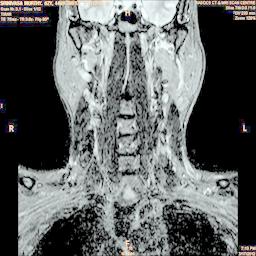

The developed algorithm presented in the previous section was coded using Matlab Version 8.0. The experiment was conducted by considering poor quality spinal cord images of having various lesions. The first column of Fig. 4 shows the axial view of neck spinal cord images of size pixels, respectively. The second column of Fig. 4 presents the same images enhanced using histogram equalization. As is evident from the results presented, the histogram equalization method performs global image enhancement operation which improves the contrast of an image but at the cost loss in image details. The third column of Fig. 4 shows the MSR based spinal cord image enhancement. It can be seen that from the result presented, MSR scheme improves the details that are not clearly visible in histogram equalization technique. In general, image enhancement achieved by MSR method is better compared to histogram equalization. However, the MSR method voilates gray world assumption. Therefore, the image enhanced by this scheme appears to be grayish. Although, numerous work have been reported for solving the problem due to gray world voilation, no work seems to developed for complete elimination.

The fourth column of Fig. 4 shows the image enhanced using Chao et al. []. It can be seen from the results presented that the reconstructed images of Chao’s method have black spots. The appearance of these dark patches degrades the visual quality of the enhanced image. The image enhanced using proposed multirate multiscale retinex image enhancement method presented in the fifth column of Fig. 4, overcomes the drawback of the Chao’s method. As we can see from the simulation results, image enhancement achieved by the proposed method has improved details with significant contrast enhancement. The enhanced images from the proposed method provides information to physicians, radiologists and researchers for various types of pathology detection.